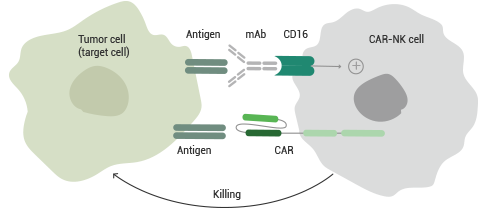

To mediate antibody-dependent cellular cytotoxicity (ADCC), NK cells recognize cell-bound antibodies via CD16A (FcγRIIIA). A new area of cancer immunotherapy is enhancing therapeutic mAb-mediated CD16 activation of NK cells.

CAR-NK cells containing multi-specific molecules made up of relatively stable CD16 and other activating receptors (e.g., NKG2D, DNAM-1/CD226, NKp46/NCR1, NKp44/NCR2, and NKp30/NCR3), scFvs for tumor antigens (e.g., CD19, CD22, ROBO1, and PSMA), and cytokine moieties (e.g. CD16 genetic modifications to eliminate sensitivity to ADAM-17-mediated proteolytic cleavage or increase affinity for IgG Fc region have shown promising results.

CAR-NK cells expressing CD16A in recombination with the high-affinity Fc receptor, CD64 (FcγRI), demonstrate a more stable and enhanced ADCC response, indicating a promising advancement in CAR-NK cell immunotherapy.

Figure 1. Mechanism of CAR-NK cell-mediated ADCC. Image Credit: Sino Biological Inc.

Figure 1 depicts the concept of using CAR-NK cells in combination with antibody immunotherapy to counteract NK cell impairment, in which CAR-NK cells can kill target cancer cells independently via CAR and also serve as CD16-positive effector cells for mitigating ADCC against cancer cells.